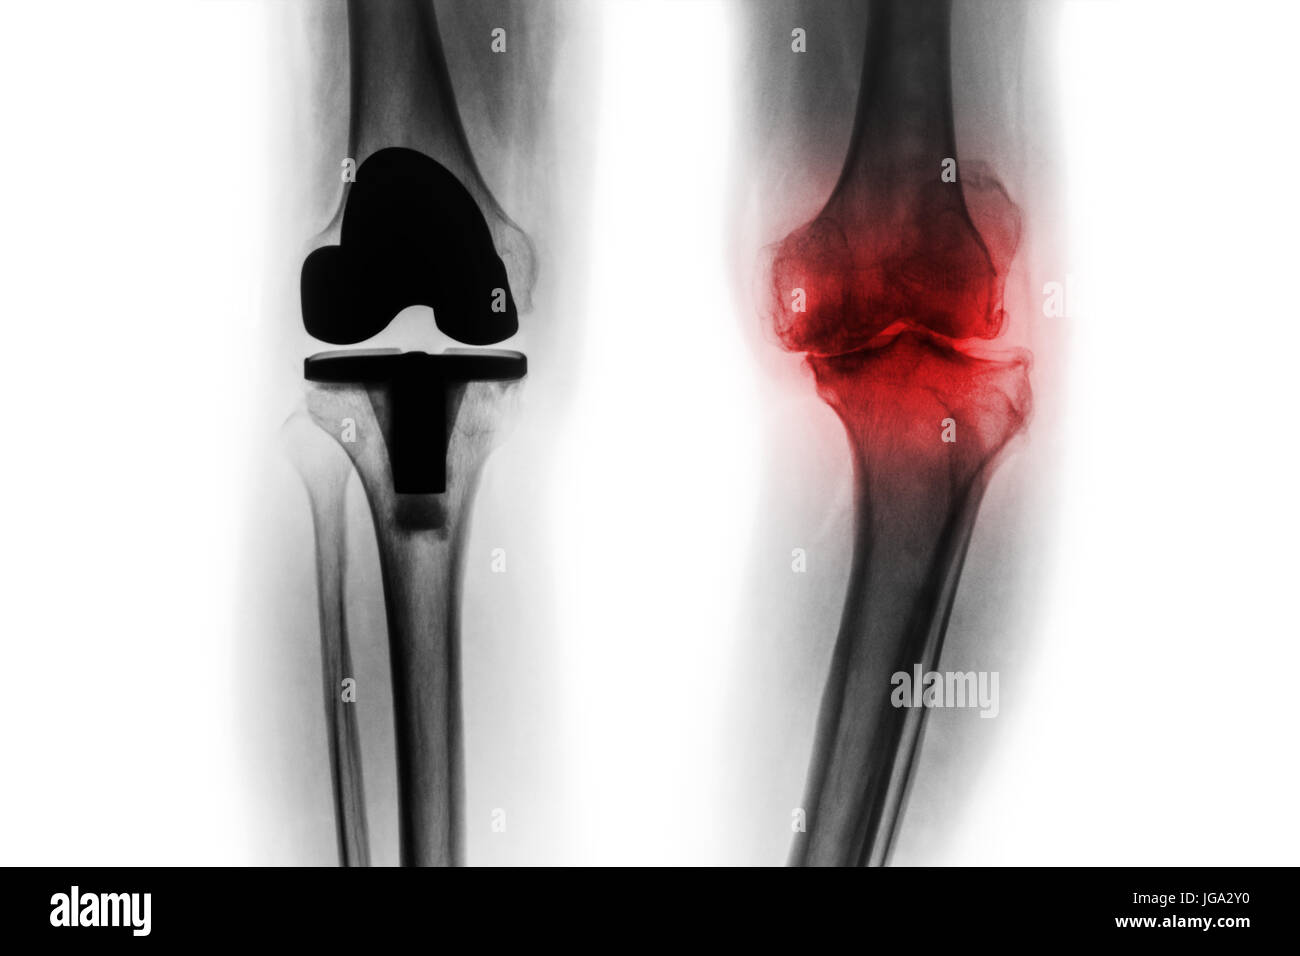

Articulation du Genou prothèse (prothèse articulaire) de l'arthrose patient Banque D'Imageshttps://www.alamyimages.fr/image-license-details/?v=1https://www.alamyimages.fr/photo-image-articulation-du-genou-prothese-prothese-articulaire-de-l-arthrose-patient-77393556.html

Articulation du Genou prothèse (prothèse articulaire) de l'arthrose patient Banque D'Imageshttps://www.alamyimages.fr/image-license-details/?v=1https://www.alamyimages.fr/photo-image-articulation-du-genou-prothese-prothese-articulaire-de-l-arthrose-patient-77393556.htmlRFEDWG7G–Articulation du Genou prothèse (prothèse articulaire) de l'arthrose patient

Film x-ray de l'arthrose du genou et patient articulation artificielle ( un remplacement total du genou ) . Fond isolé . Banque D'Imageshttps://www.alamyimages.fr/image-license-details/?v=1https://www.alamyimages.fr/photo-image-film-x-ray-de-l-arthrose-du-genou-et-patient-articulation-artificielle-un-remplacement-total-du-genou-fond-isole-147739277.html

Film x-ray de l'arthrose du genou et patient articulation artificielle ( un remplacement total du genou ) . Fond isolé . Banque D'Imageshttps://www.alamyimages.fr/image-license-details/?v=1https://www.alamyimages.fr/photo-image-film-x-ray-de-l-arthrose-du-genou-et-patient-articulation-artificielle-un-remplacement-total-du-genou-fond-isole-147739277.htmlRFJGA2XN–Film x-ray de l'arthrose du genou et patient articulation artificielle ( un remplacement total du genou ) . Fond isolé .

Film x-ray de l'arthrose du genou et patient articulation artificielle ( un remplacement total du genou ) . Fond isolé . Banque D'Imageshttps://www.alamyimages.fr/image-license-details/?v=1https://www.alamyimages.fr/photo-image-film-x-ray-de-l-arthrose-du-genou-et-patient-articulation-artificielle-un-remplacement-total-du-genou-fond-isole-147739284.html

Film x-ray de l'arthrose du genou et patient articulation artificielle ( un remplacement total du genou ) . Fond isolé . Banque D'Imageshttps://www.alamyimages.fr/image-license-details/?v=1https://www.alamyimages.fr/photo-image-film-x-ray-de-l-arthrose-du-genou-et-patient-articulation-artificielle-un-remplacement-total-du-genou-fond-isole-147739284.htmlRFJGA2Y0–Film x-ray de l'arthrose du genou et patient articulation artificielle ( un remplacement total du genou ) . Fond isolé .

Film x-ray de l'arthrose du genou et patient articulation artificielle ( un remplacement total du genou ) . Fond isolé . Banque D'Imageshttps://www.alamyimages.fr/image-license-details/?v=1https://www.alamyimages.fr/photo-image-film-x-ray-de-l-arthrose-du-genou-et-patient-articulation-artificielle-un-remplacement-total-du-genou-fond-isole-147739271.html

Film x-ray de l'arthrose du genou et patient articulation artificielle ( un remplacement total du genou ) . Fond isolé . Banque D'Imageshttps://www.alamyimages.fr/image-license-details/?v=1https://www.alamyimages.fr/photo-image-film-x-ray-de-l-arthrose-du-genou-et-patient-articulation-artificielle-un-remplacement-total-du-genou-fond-isole-147739271.htmlRFJGA2XF–Film x-ray de l'arthrose du genou et patient articulation artificielle ( un remplacement total du genou ) . Fond isolé .

Film x-ray de l'arthrose du genou et patient articulation artificielle ( un remplacement total du genou ) . Fond isolé . Banque D'Imageshttps://www.alamyimages.fr/image-license-details/?v=1https://www.alamyimages.fr/photo-image-film-x-ray-de-l-arthrose-du-genou-et-patient-articulation-artificielle-un-remplacement-total-du-genou-fond-isole-147739268.html

Film x-ray de l'arthrose du genou et patient articulation artificielle ( un remplacement total du genou ) . Fond isolé . Banque D'Imageshttps://www.alamyimages.fr/image-license-details/?v=1https://www.alamyimages.fr/photo-image-film-x-ray-de-l-arthrose-du-genou-et-patient-articulation-artificielle-un-remplacement-total-du-genou-fond-isole-147739268.htmlRFJGA2XC–Film x-ray de l'arthrose du genou et patient articulation artificielle ( un remplacement total du genou ) . Fond isolé .